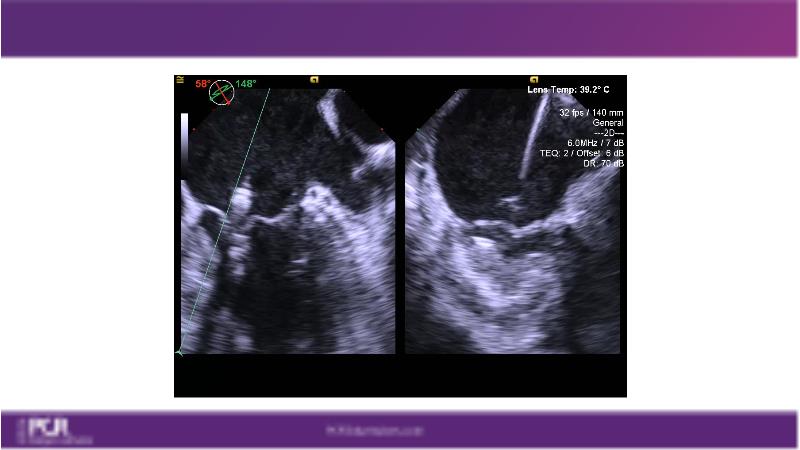

Watch this session to get an overview of a new TEER device, follow the step-by-step procedure related to initial experiences with this device for a Japanese patient with degenerative mitral regurgitation, learn about the latest data from RCT and registries, and follow discussions of challenging TEER cases!

- To learn procedural step-by-step of novel device